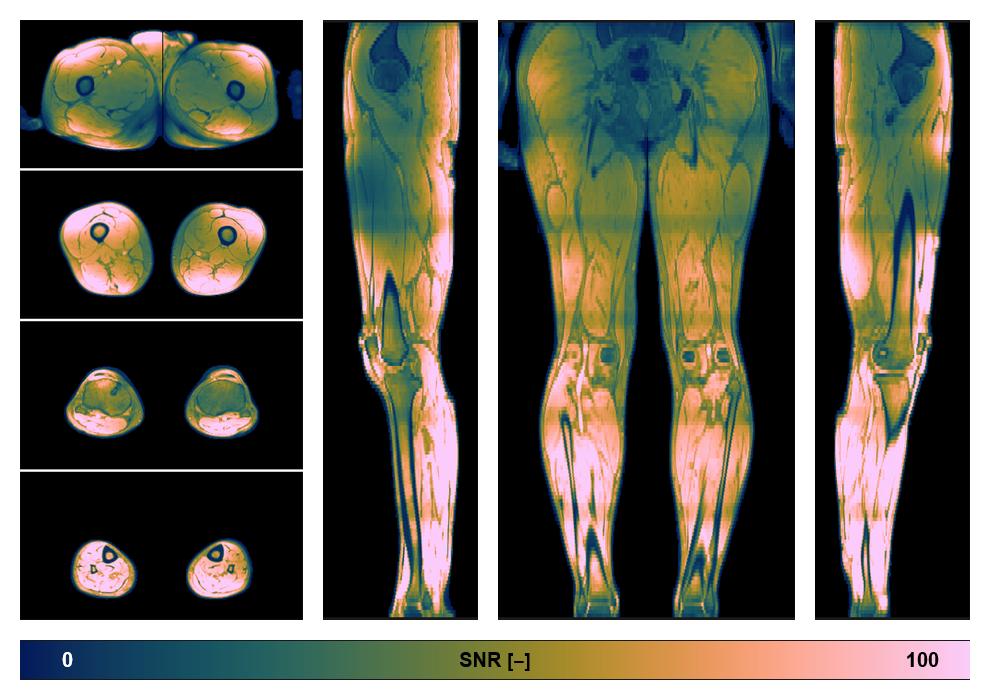

• SNR of the unweighted image

SNR distribution of the unweighted diffusion data.